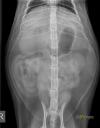

RadioQuiz 24 – Abdomen gonflé et tendu